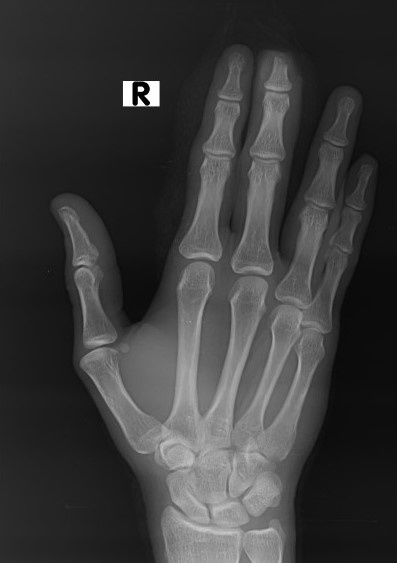

🚨 Разбор вчерашнего кейса! 🚨 Инструментальная травма на производстве. Данные о пациенте Возраст: 30 лет Пол: Мужчина У пациента выставлен диагноз СД 2 типа Обсуждение конкретного случая. Результаты соответствуют травматической поперечной ампутации кончика пальца третьей дистальной фаланги с повреждением кости и мягких тканей. ❗Травматическая ампутация дистальной фаланги часто происходит в результате несчастных случаев, приводящих к повреждению мягких тканей и потенциальному остеомиелиту, особенно у пациентов с диабетом❗ (Планирую проводить 1-2 раза в неделю такие разборы РГ снимков если вам это интересно ставьте 🔥)

Результаты соответствуют травматической поперечной ампутации кончика пальца третьей дистальной фаланги с повреждением кости и мягких тканей.

❗Травматическая ампутация дистальной фаланги часто происходит в результате несчастных случаев, приводящих к повреждению мягких тканей и потенциальному остеомиелиту, особенно у пациентов с диабетом❗